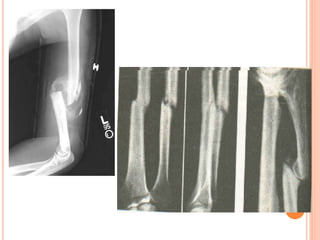

PERDA SANGUINEA INTERNA ASSOCIADA À FRATURAS

Osso fraturado Perda sanguínea (ml)

Costela 125

Radio ou ulna 250 a 500

Úmero 500 a 750

Tíbia ou fíbula 500 a 1000

Fêmur 1000 a 2000

Bacia 1000

FRATURAS

Fratura Fechada: Trauma sem rompimento da pele.

Fratura Aberta: Trauma com rompimento da pele.

Fratura com angulação (desvio): Uma fratura que faz